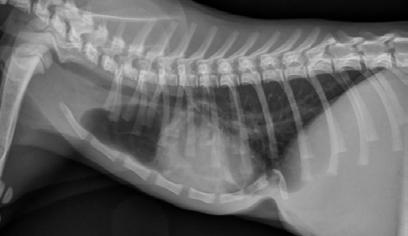

She was assessed as a case of severe pectus excavatum. On CBC, her PCV was found to be 0.18 L/L, total plasma protein concentration 57g/L; the anaemia was suspected to be from the heavy flea burden she had when found. Radiographs were taken under sedation which showed marked compression of the thoracic cavity with the heart displaced to the right side ( Figure 2).

The ears were then looped through the cast which was moulded to the correct shape using a 20 mL syringe and pulled tight to pull sternum ventrally. No complications were encountered at this stage. Post-op radiographs showed marked improvement in the position of the sternum. RR was 60/minute.